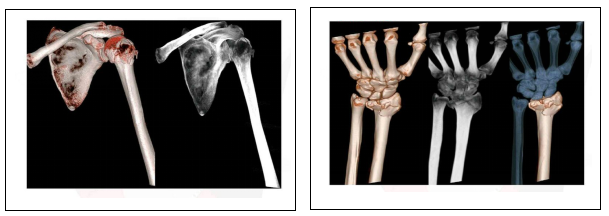

三.骨科系统:

可以沿任意轴观察骨骼,任意角度重建可以发现隐匿的骨折、复杂多发骨折、骨折手术效果评估。

左侧肱骨头骨折 桡骨头骨折